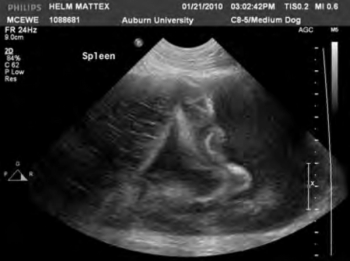

Sometimes, splenectomies are straightforward and predictable. Other times, not so much. A veterinary surgeon shares tips for getting better outcomes in splenic torsion cases.